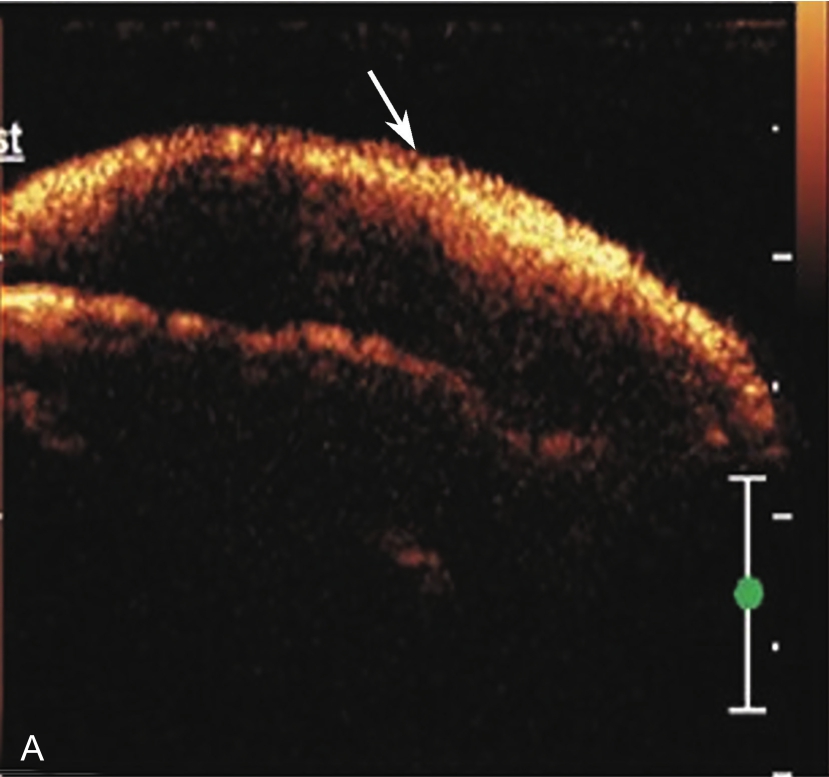

3.当肩袖回声不均匀,有可疑的滑囊面撕裂或全层撕裂,行超声引导下肩峰下-三角肌下滑囊造影检查,可提高对肩袖撕裂的诊断率。方法:将2~5ml生理盐水与0.5ml的超声造影剂混合后,注入肩峰下-三角肌下滑囊,无撕裂的滑囊呈线状高增强(图2-1-8),肩袖滑囊面部分撕裂可见造影剂混合液从滑囊进入肩袖肌腱内而未达肱骨头表面(图2-1-9),若观察到其进入肩关节腔或肱二头肌长头腱鞘,则诊断肩袖全层撕裂(图2-1-10)。

▲ 图2-1-8 超声引导下肩峰下-三角肌下滑囊造影图(一)

A.超声引导下滑囊内注入超声造影剂后,滑囊呈线状高增强(箭头);B.注入造影剂后的滑囊(箭头),冈上肌腱(SUP)连续性好,未见撕裂,HH:肱骨头